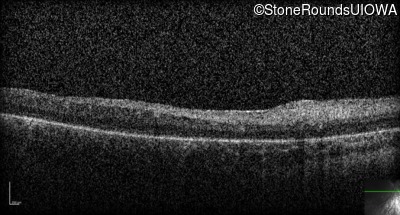

Optical Coherence Tomography - Right -

No Light Perception

Exemplar

Expanded OCT Stack

×